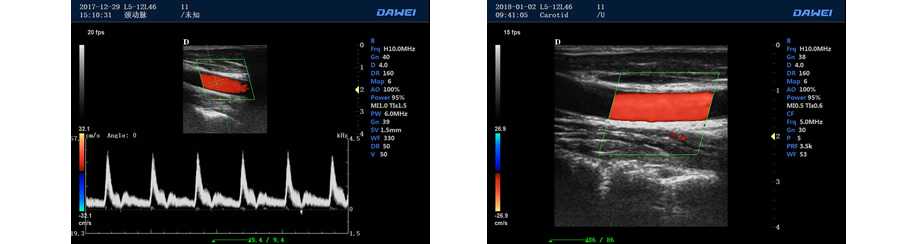

多普勒模式

具有PW脈沖波多普勒和CW連續波多普勒

取樣容積大小,可視可調

采樣角度校正:-30-80度

脈沖重復頻率多段可調

外周血管 多普勒血流測量與分析